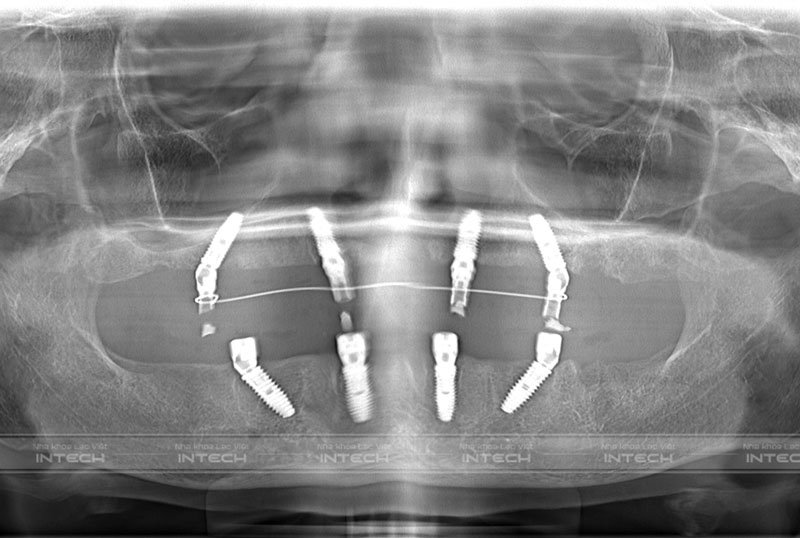

Qua thăm khám và chụp phim X-quang, bác sĩ Vũ Đức Duy - Chuyên gia cấy ghép Implant tại Nha khoa Lạc Việt Intech nhận định: “Cô Tô Thị Hải bị mất nhiều răng lâu năm và đã làm cầu răng sứ sai cách. Hiện tại, cầu răng của cô đã bị rơi ra. Đây là hậu quả của việc làm cầu sứ sai cách và điều trị tủy không tốt”.

Hình ảnh phim chụp CT của cô Tô Thị HảiHình ảnh phim chụp CT của cô Tô Thị Hải

Để khôi phục lại chức năng ăn nhai cũng như tính thẩm mỹ 2 hàm răng cho bệnh nhân, bác sĩ đã đưa ra giải pháp điều trị trồng răng Implant All On 4 toàn 2 hàm. Kỹ thuật trồng răng All On 4 được thực hiện bằng cách cấy 4 trụ Implant trong 1 hàm để nâng đỡ 12 chiếc răng trên cung hàm.

Trong đó có 2 trụ Implant được cấy tại vị trí răng số 2 và 2 trụ Implant được cấy nghiêng một góc tại vị trí răng số 5. Sự hỗ trợ của Multi-unit Abutment có tác dụng liên kết trụ Implant và hàm giả cố định chắc chắn, đảm bảo chức năng ăn nhai như răng thật.